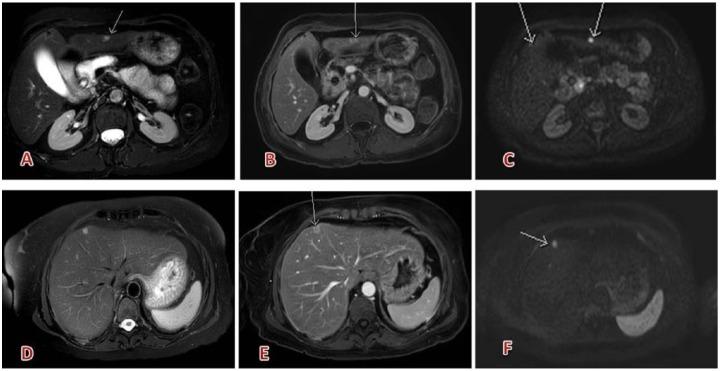

Gadobutrol is a gadolinium (Gd)-based contrast agent for magnetic resonance imaging (MRI). In India, gadobutrol is approved for MRI of the central nervous system (CNS), liver, kidneys, breast and for MR angiography for patients 2 years and older. The standard dose for all age groups is 0.1 mmol/kg body weight. The safety profile has been demonstrated in 42 clinical phase 2 to 4 studies (>6800 patients), 7 observational studies, and by assessing pharmacovigilance data of 29 million applications. Furthermore, studies in children, adults, and elderly and in patients with impaired liver or kidney function did not show any increased adverse event rate. Diagnostic efficacy was demonstrated in numerous studies and various indications, such as diseases of the CNS, peripheral and supra-aortic vessels, kidneys, liver, and breast.

钆布醇是一种用于磁共振成像(MRI)的基于钆(Gd)的造影剂。在印度,钆布醇被批准用于2岁及以上患者的中枢神经系统(CNS)、肝脏、肾脏、乳腺的MRI检查以及磁共振血管造影。所有年龄组的标准剂量为0.1 mmol/kg体重。在42项2期至4期临床研究(>6800例患者)、7项观察性研究以及通过评估2900万份用药的药物警戒数据中均已证明了其安全性。此外,在儿童成人、老年人以及肝肾功能受损患者中进行的研究并未显示不良事件发生率有任何增加。在众多研究以及各种适应症(如中枢神经系统疾病、外周和主动脉上血管疾病、肾脏疾病、肝脏疾病和乳腺疾病)中均证实了其诊断效能。